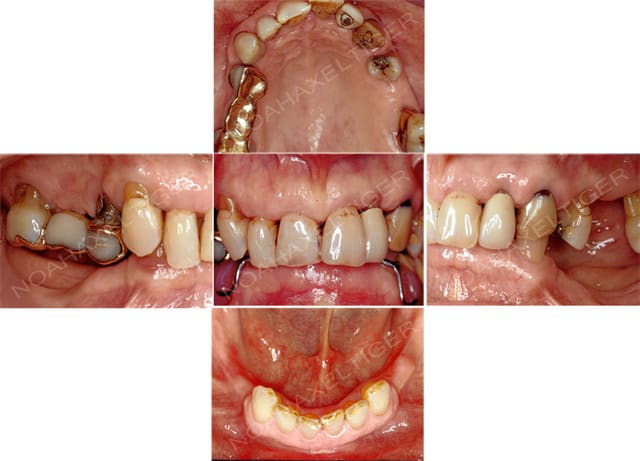

J'ai traité il ya de cela quelque temps un cas de réhabilitation globale sur terrain paro. Comme toi ikimine j'ai du faire face à un effondrement de DV, ce qui m'a amené à combiner paro, implanto, prothétique conventionnelle et occluso.

Voila les photos et radios initiales :

Initial ou2oph - Eugenol

Dents jugées comme devant extraites : 16, 14, 12, 24, 27

Dents jugées comme ayant un pronostic incertain : 22, 23

Facteurs importants à prendre en compte pour le plan de traitement : hauteur osseuse sous sinusienne réduite, crête très fine à la mandibule.

Souhait de la patiente : rehabilitation fixe au maxillaire. A la mandibule, la patiente est déja porteuse d'une PPAC qu'elle accepte parfaitement. La patiente souhaite seulement une meilleure rétention mais ne veut pas se lancer dans des travaux d'augmentation osseuse importants.

Plan de traitement :

1-analyse occlusale globale. Waxup. Assainissement parodontal

2-extraction de 16, 14, 12, 24, 27. Préparation de 13,11,21,22,23 et mise en place d'un bridge provisoire + PP issus du waxup initial.

3-sinus lyft avec abord crestal et implantation de 16, 15, 14, 24, 25, 26. Implant en 44.

4-chirurgie mucogingivale au niveau du bloc incisivocanin supérieur

5-bridge implantoporté 16,15,14 - bridge conventionnel 13,11,21,23 - Bridge implantoporté 24,25,26

6-attachement boule 44 - attachement extracoronaire boule 34 - PPAC mandibulaire.